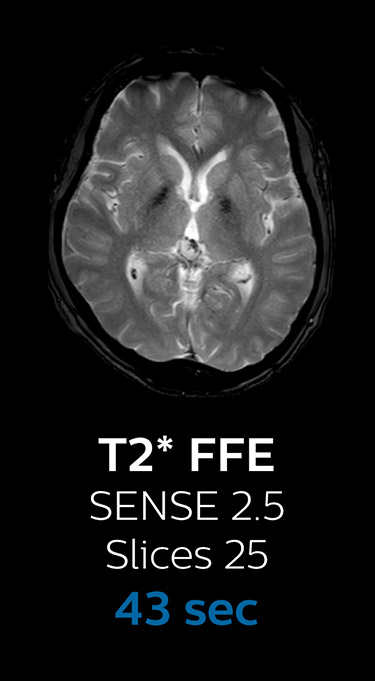

“We now only need about 10 minutes of scan time for a brain exam – and we still get the same amount of images and equal quality. We even managed to make a very useful improvement: we replaced the 43-second T21 FFE by a 43-second SWIp, which is more powerful for us in making confident diagnoses in certain patients.” “SWIp was not previously included in our standard protocol, because of its slightly longer scan time. SWIp provides high resolution 3D susceptibility weighted imaging in the brain, which helps to visualize small deoxygenated blood or calcium deposits. Now, with Compressed SENSE, we can perform 3D SWIp in only 43 seconds, so we have included SWIp instead of the 2D T21 FFE that we used previously. Without adding scan time, we now get SWIp images in every routine brain scan and it helps us increase our diagnostic confidence in certain cases.”

The most frequently used brain MRI examination at KNC included approximately 15 minutes of scanning time, and was quite comprehensive with fairly short scan times. When Compressed SENSE became available, its great impact on the brain exam quickly became clear.

Fast MRI of brain

With Compressed SENSE, the scan time for the routine brain examination at KNC was reduced from 15:48 to 10:19 minutes, which corresponds to 35% reduction.

Ingenia 3.0T CX

Scan time 15:48 min.

Brain with Compressed SENSE

Ingenia 3.0T CX

Scan time 10:19 min.